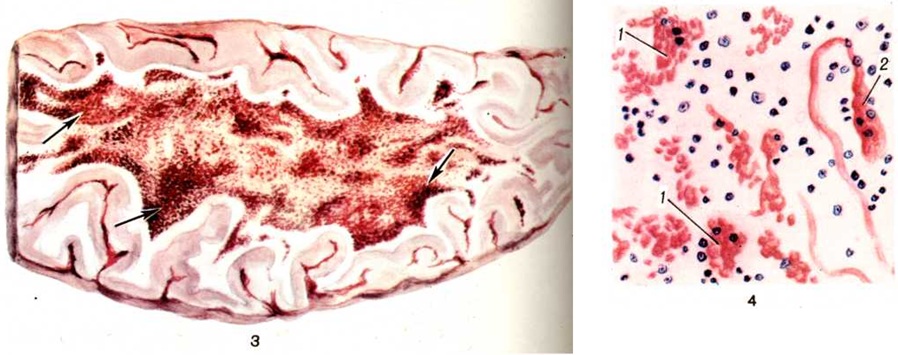

Весьма характерными для периода спазматического кашля являются расстройства кровообращения, связанные с каш левыми пароксизмами; последние обусловливают частые периоды резкого застоя в системе верхней полой вены, в частности в области головы и шеи, с появлением кровоизлияний в конъюнктиве глаз, коже лица в области век у внутреннего угла глаза, в слизистой оболочке полости рта и носа, реже — в передней камере глаза, внутреннем ухе. В мозговых оболочках и веществе головного мозга наблюдаются циркуляторные нарушения — гиперемия, отёк, стазы и кровоизлияния (цветной рисунок 3 и 4). Следствием гемодинамических нарушений, сопровождающихся гипоксией, могут явиться некробиотические изменения нервных клеток, их гибель с последующей глиальной реакцией.